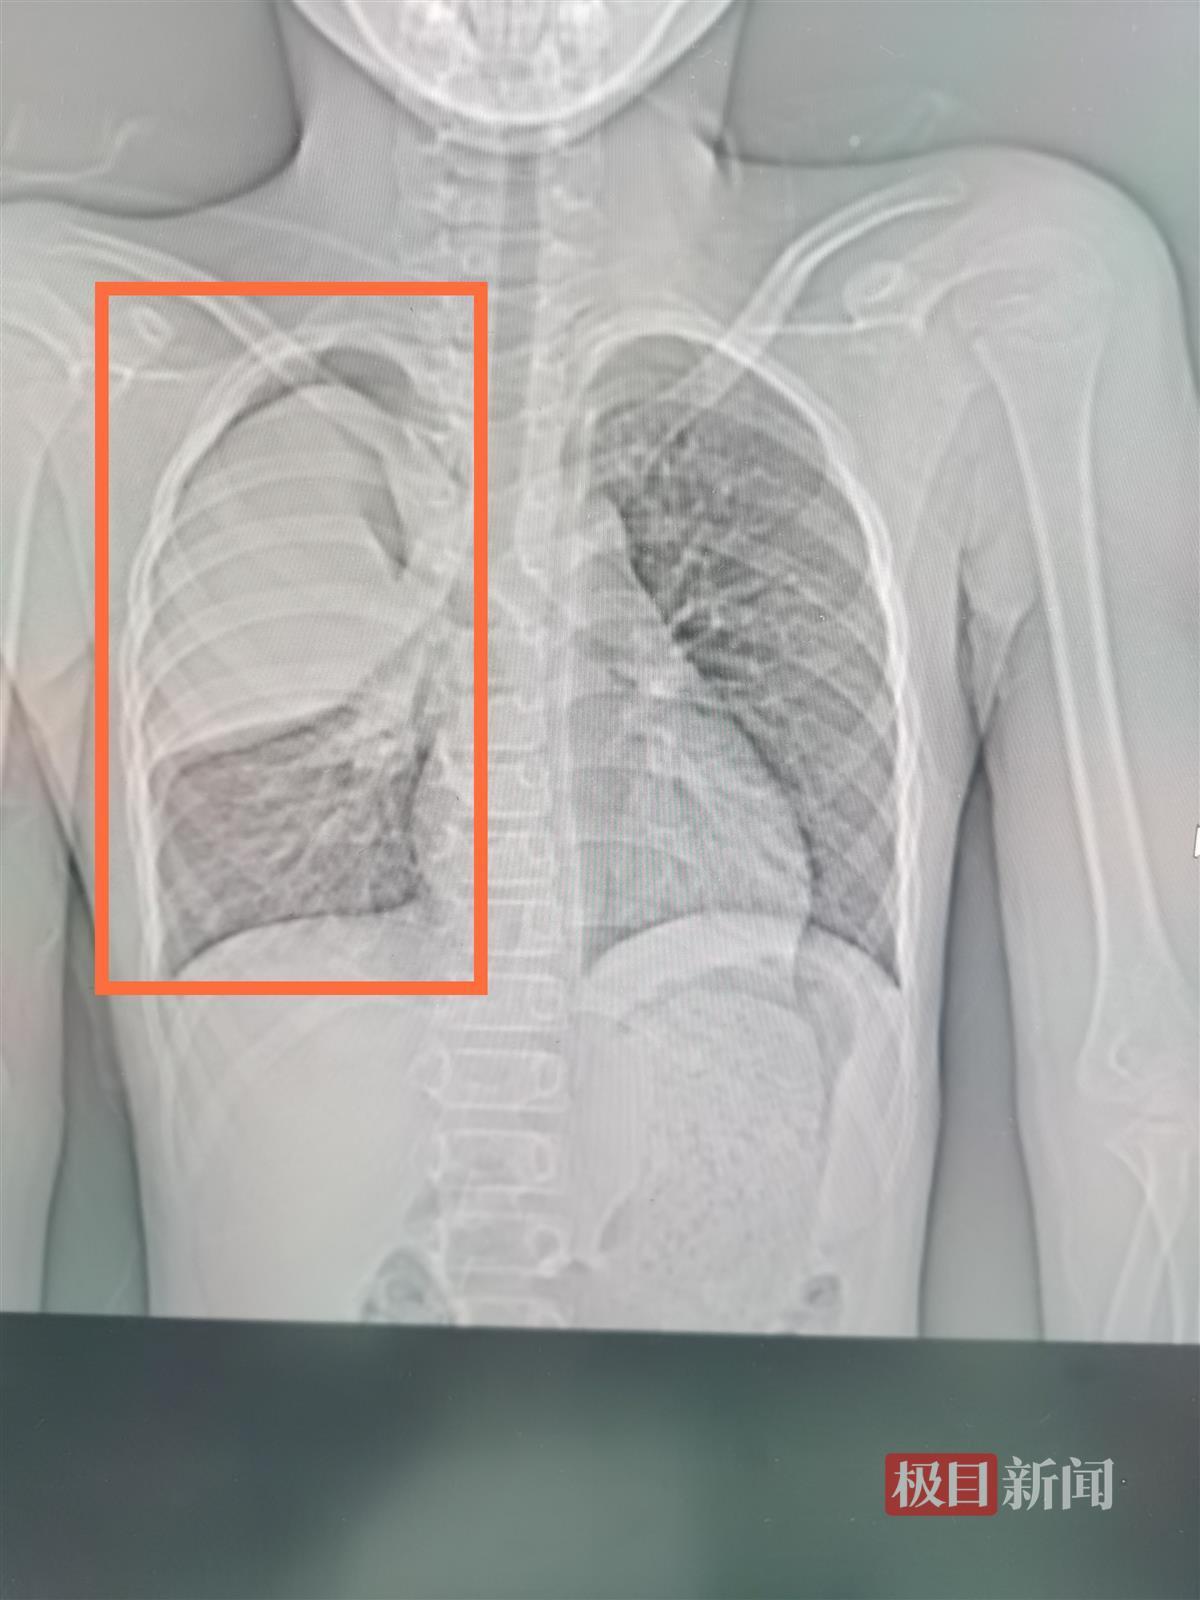

右上肺三分之二出现白肺

该院呼吸二病区副主任杨澄清说,CT检查发现,孩子的右肺“大片状实变”,也就是常说的“白肺”。通过相关检查,小阳的支原体抗体呈阳性,肺炎支原体核酸阳性,随即确诊为肺炎支原体肺炎。目前,小阳的病情已得到控制,并趋于康复。